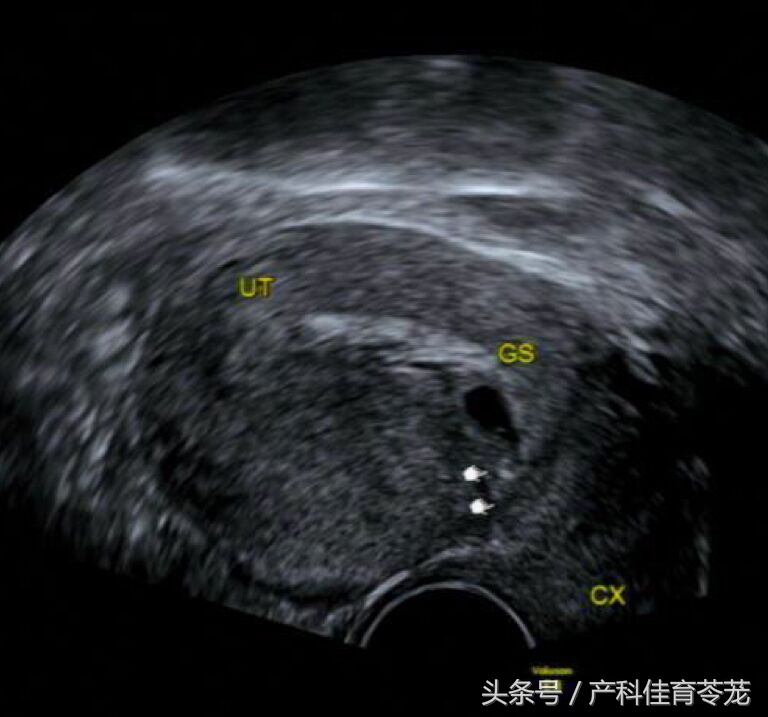

出血的原因是因为孕囊种植在原来瘢痕的位置,专业术语为“瘢痕妊娠(cesarean scar pregnancy,CSP)”,就是这样:

CSP 首选经阴道彩色多普勒超声结合经腹超声进行诊断:

诊断依据*:

子宫前壁瘢痕处见胎囊着床或不均质团块;

子宫宫腔及颈管处未见妊娠囊;

前壁瘢痕处肌层连续性中断,肌层变薄;

彩色多普勒超声显示瘢痕处胎囊或包块周围见高速低阻血流,阻力指数一般为 0.4~0.5mJ。